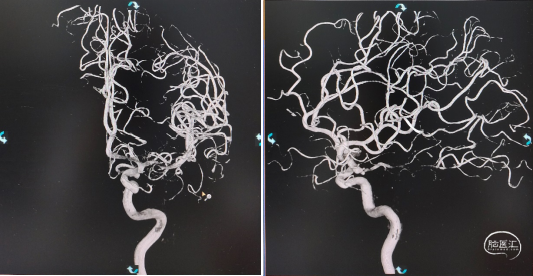

造影所见:双侧颈动脉血管稍迂曲僵硬,双侧后交通动脉开放,左侧颈内动脉后交通段可见一“囊状”突起,大小约6.19mm*4.07mm*2.35mm,瘤颈4.03mm,基底宽,边缘不光整,有两个子瘤,指向后下方,后交通动脉从瘤颈处发出。

3D